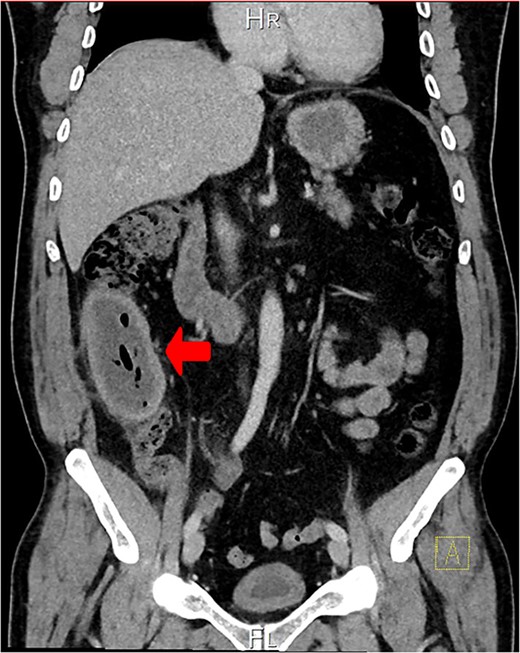

A CT scan showed an oval, 13 × 5.2 cm mass in the right iliac fossa arising from the cecum and running upward, with a thick, edematous wall, fluid, gaseous content, and extensive fat stranding. There was no free fluid and no dilation of bowel, suggesting appendicitis (Figs 1 and 2). Due to these findings, the patient underwent an emergency laparoscopic appendectomy that was converted to open laparotomy. The patient ended up with a right hemicolectomy instead of appendectomy as the appendix could not be separated from the mass, with no separation line between the mass and the cecum. The mass (Fig. 3) measured 10 × 7 × 7 cm and had a thick wall and pyogenic membrane.

A coronal CT view reveals an oval mass in the right iliac fossa. The mass has a thick, edematous wall and contains fluid and gas. Extensive fat stranding is visible, but no free fluid or bowel dilation is noted.